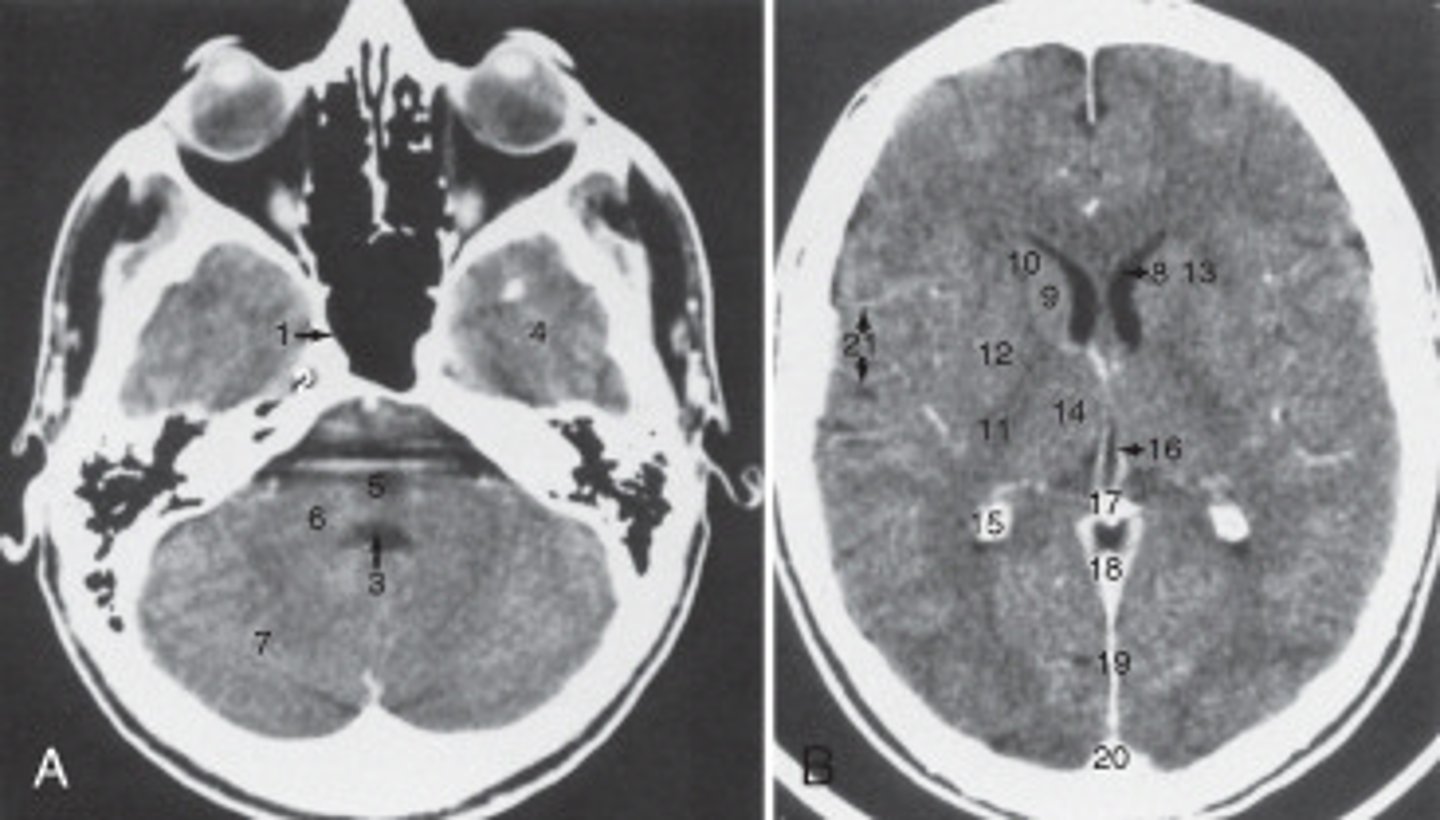

8

The anterior (frontal) horn of the lateral ventricle is labeled as:

<p>The anterior (frontal) horn of the lateral ventricle is labeled as:</p>

14

The thalamus is labeled:

<p>The thalamus is labeled:</p>

19

the fall cerebri is labeled:

<p>the fall cerebri is labeled:</p>

calcified choroid plexus

The structure labeled 15 is the:

<p>The structure labeled 15 is the:</p>

fourth ventricle

The structure labeled 3 is the:

<p>The structure labeled 3 is the:</p>

cerebellar hemisphere

The structure labeled as 7 is the:

<p>The structure labeled as 7 is the:</p>